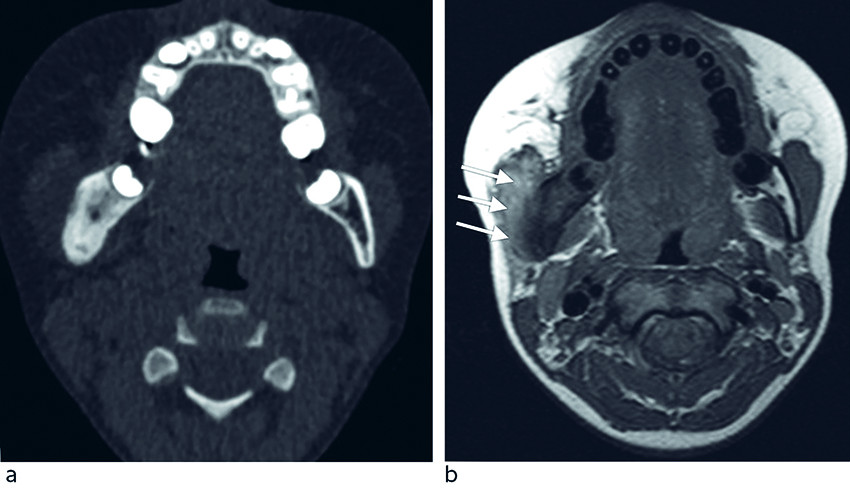

Ved klinisk undersøkelse observerte man asymmetri i ansiktet og en fast, lett palpasjonsøm hevelse på ca. 3 cm langs høyre underkjeve uten infeksjonstegn i huden eller tennene. MR- og CT-undersøkelse viste ekspandert ben med ødem i høyre underkjeve og kontrastoppladning i omliggende bløtvev (figur 3).

Intraoralt var det ingen tegn til fistler, infeksjon eller tannpatologi. CT-undersøkelse viste betydelig oppdriving i tyggemuskulatur, fortykket underkjeve og forstørrede lymfeknuter på venstre side, som radiologisk ble tolket som kronisk osteomyelitt.